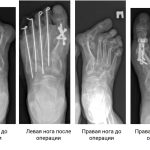

НИИТО, да не то

Судьбу уникального медицинского учреждения федеральный Минздрав будет решать с учетом позиции депутатов Законодательного собрания

ВОТ уже восемь месяцев 800 сотрудников Новосибирского научно-исследовательского института травматологии и...